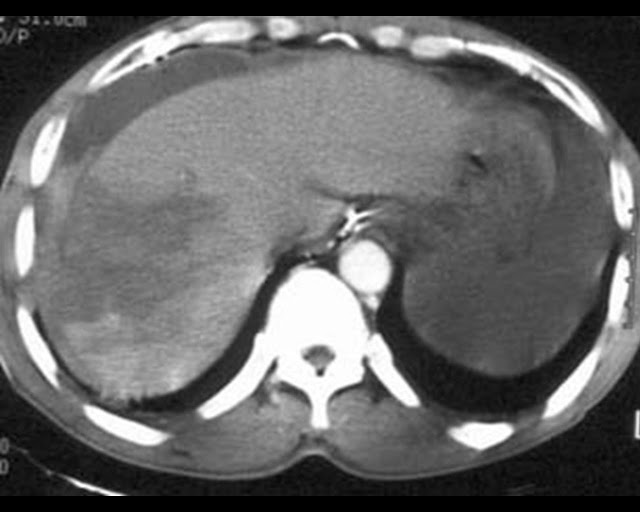

I’ve never quite been sure of the derivation of the phrase. A perfect example of its use is in a slide such as this.

There is simply so much “going on” in this image that the audience will be unable to derive meaning from any of the images (or worse still from the speech) because they are trying to decide which image to actually look at. Help the audience and simply project each image as required. (It’s a Grade IV Liver laceration)